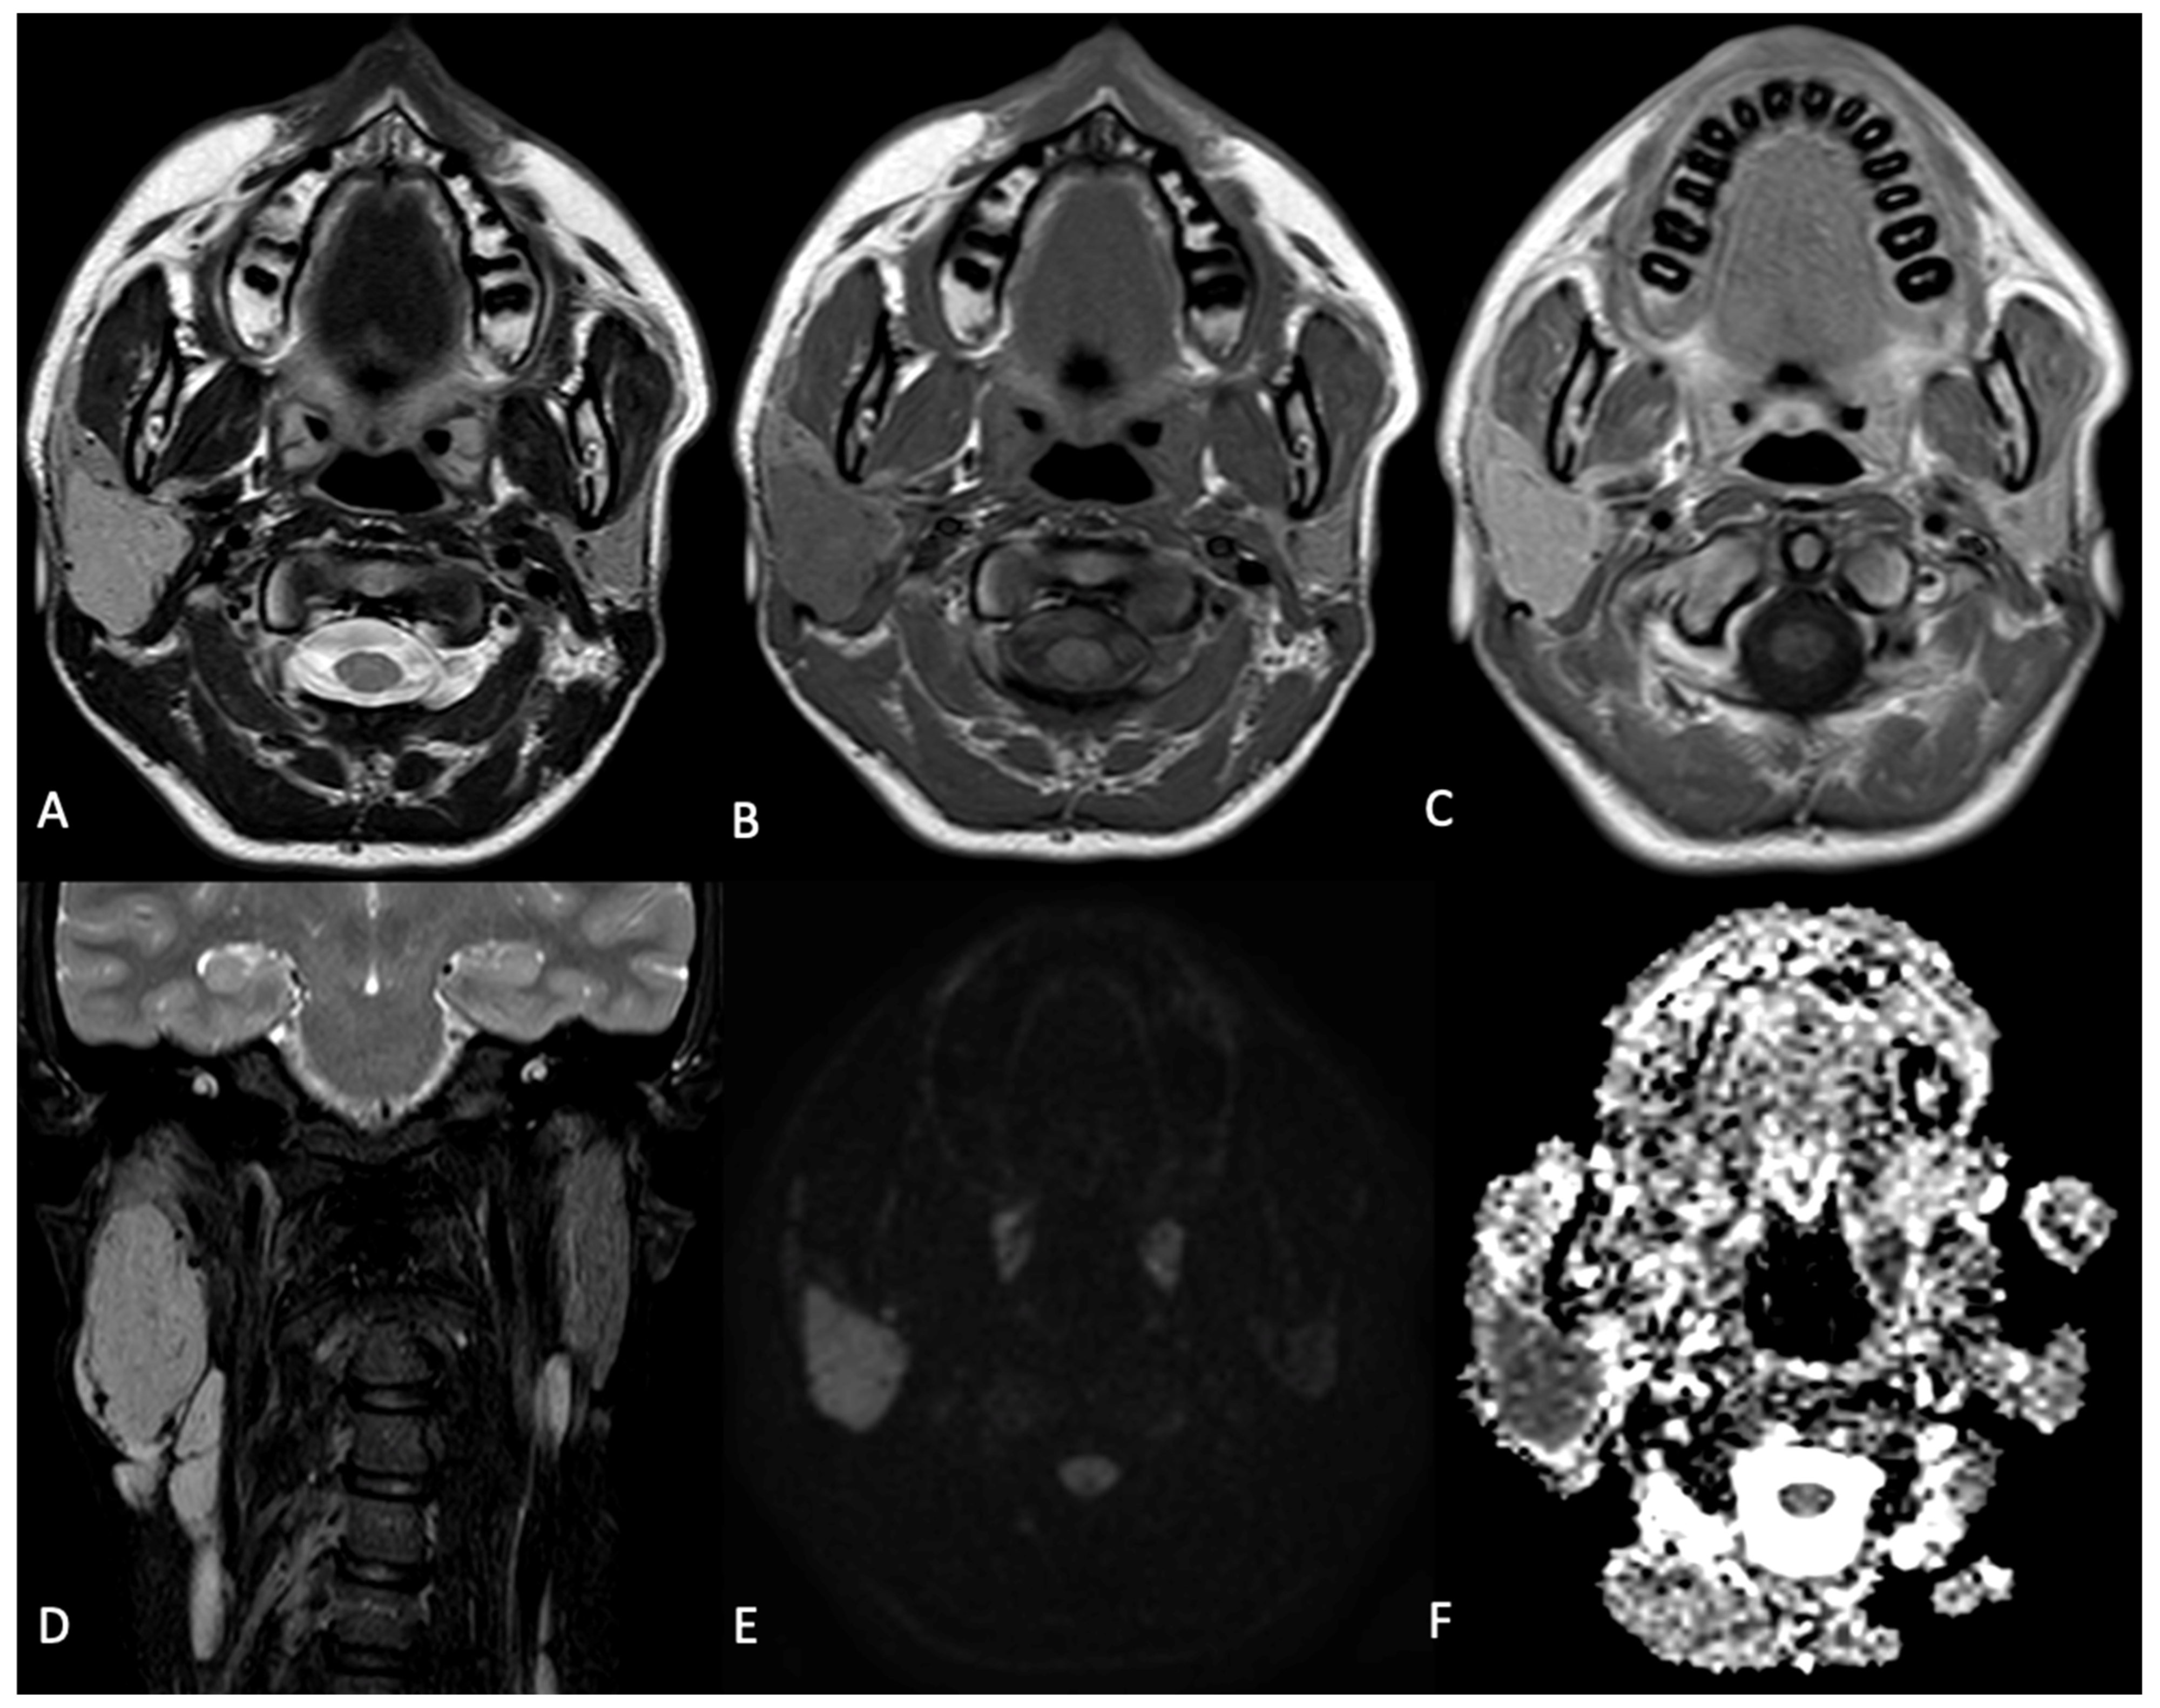

2. Case